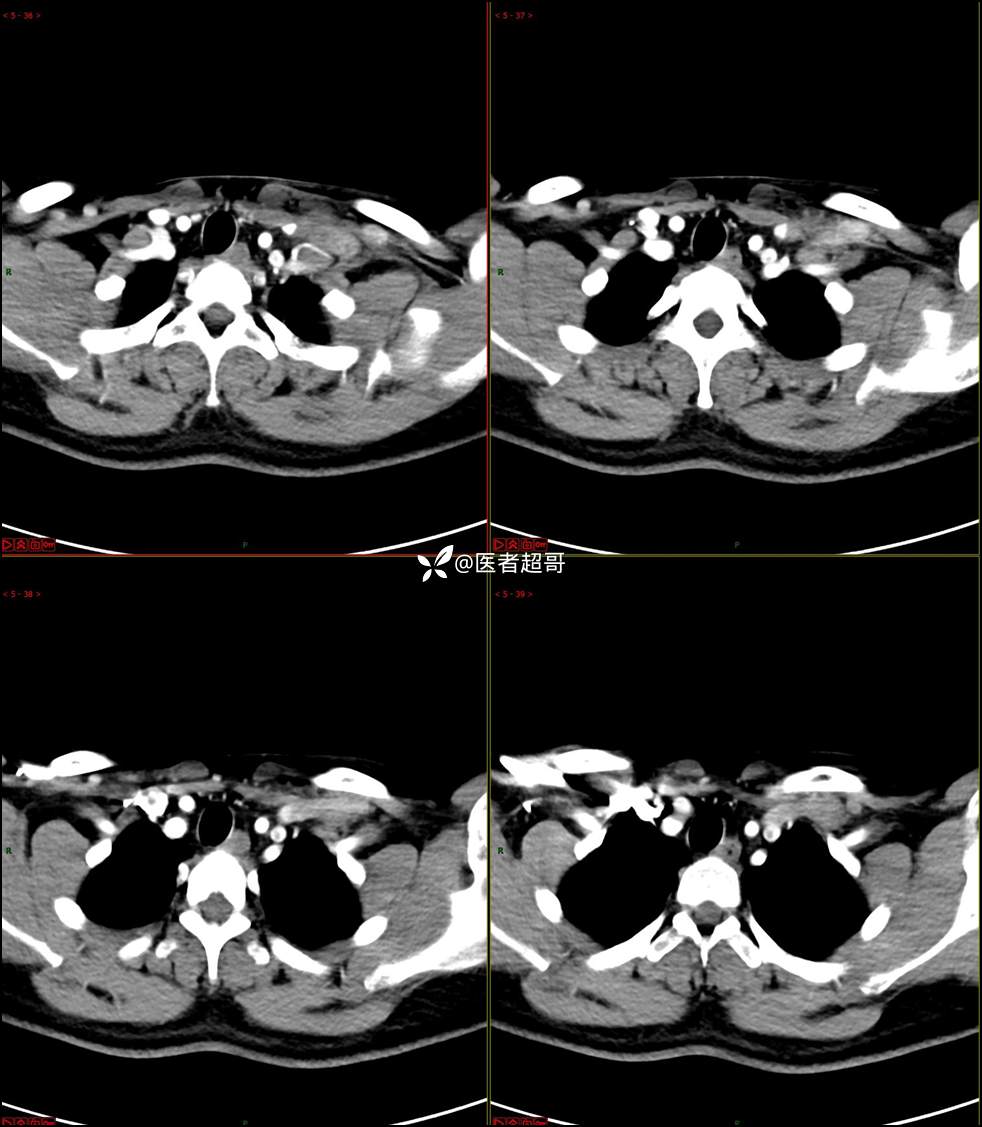

现病史:患者自述10余天前无意中发现左侧颈部一肿物,颈部活动时、进食时伴疼痛,无发热,患者前往人民医院就诊,给予输液治疗(头孢呋辛钠2g bid 硫酸阿米卡星0.4g qd、)10天,患者感肿物轻微变小,后患者为求进一步治疗,昨日来我院门诊就诊,给予颈部彩超示:左颈部实性肿物,神经来源?,左颈部肿大淋巴结;颈部ct平扫+强化示:左侧锁骨上区占位,神经鞘瘤?双侧颈部多发淋巴结;门诊以“局部肿物”收治入院,患者自患病以来,神志清,精神可,饮食睡眠可,体重无明显变化,二便正常。